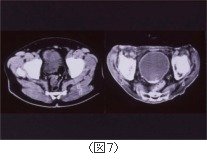

この為、クロナキシーメーターを用いてS−D曲線を求めたところ、正常な双曲線が得られたにもかかわらず、長期臥床群では体圧分散効果が認められなかった事は、図7に示した様に

正常例(著者)に比して長期臥床例ではすでに廃用性筋萎縮を生じ、殿部筋群が収縮しても体圧を分散さしめるストロークが生じ得ない為と考えられた。支持組織である殿部筋群の萎縮は仙骨部の圧力勾配を増強さしめ、より多くの張力、剪断力が発生すると考えられた。正常群のBMI高値例では圧力勾配が小さい事から、皮下脂肪も重要な支持組織であると考えられ、自律神経系の関与をも含めた組織全体の緊張度について、今後の検討課題と思われた。tcPO2,tcPCO2を用いた検討は、皮膚組織が43℃の加温を要すなど測定原理上の特性1)を考慮する必要はあるが、循環不全による酸素供給の途絶と二酸化炭素の運び出しの障害によりtcPO2が低下しtcPCO2が上昇する。褥創発生に関する圧力と時間の反比例の関係はReswickとRoger2)により閾値曲線が提示されており、60mmHgの圧力負荷3)を加えたところ、tcPO2は0のままtcPCO2は時間に比例して上昇した事から、この状態が続けば皮膚組織は不可逆的変化を呈すると考えられた。10分間経過時点つまりT.U.V群の条件開始時点のtcPO2はいずれも0torr、tcPCO2は各々97、98、93torrであり、T.V.V群とも5分間で、正常値に回復し得た。圧力負荷が継続されたU群に於いても、2Hzの断続的な通電によって不可逆的過程の防止が可能であった。骨格筋は活動により血流量が安静時の30倍に増加し、熱産生も増加する、V群のtcPO2の回復がやや優位か?とも考えられた理由として、電気刺激による筋活動が、すでに43℃の加温状態であった皮膚毛細循環の血管床をも、さらに加温増加させたとは考え難く、皮下に位置する筋活動が皮膚の毛細循環に能動的に働いた為か等、今後の再検討課題である。 |